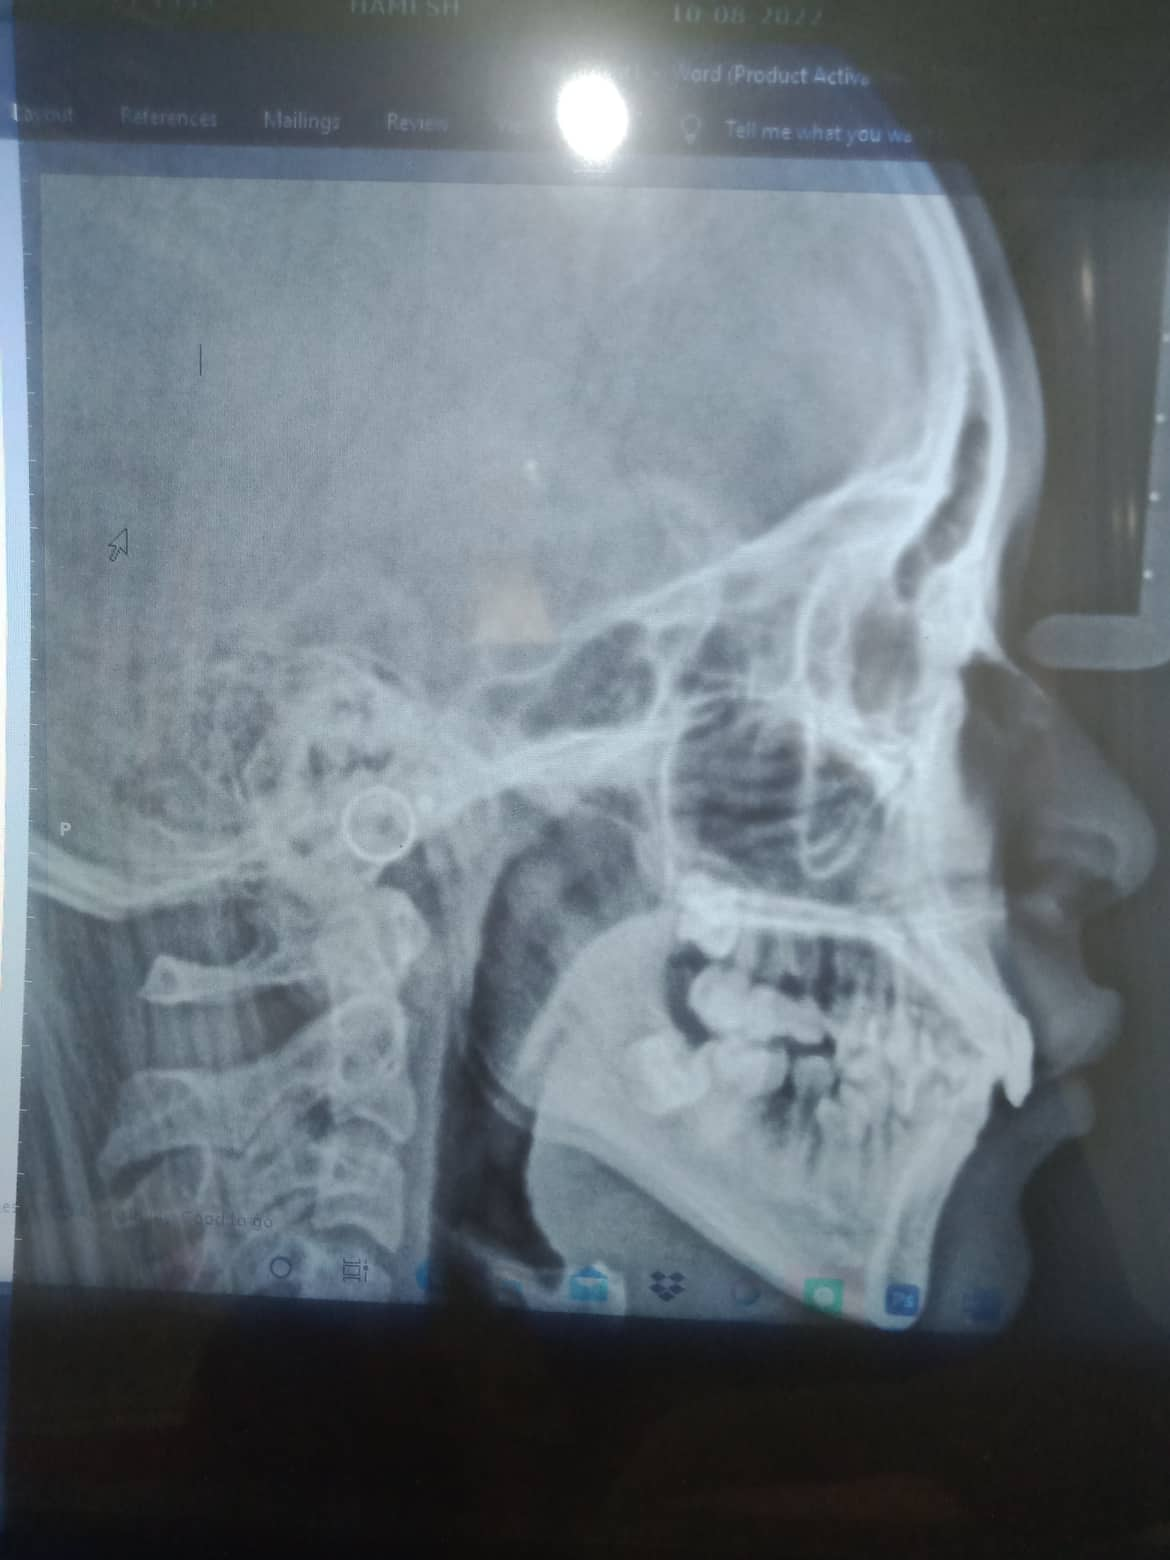

Edit Record Check our patient data records. Add patient information Patient Info Profile picture Last Name First Name Middle Name Birthdate Age Street Barangay City Country Zip Code Contact number Email Procedure 10/01/22 - OP(L), EXO #16, #46, GIVEN POST OP INSTRUCTIONS 10/08/22 - RESTO #11(LINGUAL/DISTAL), #22(MESIAL/LABIAL), MBT 0.22slot 14niti (upper), no brackets on lower *for extraoral photos 1/21/23- Upper Same wire, lower install brackets Install occlusial pads #47,#36 11/26/22--Lc 01/21/23-Upper-Same wire/L install bracket/ install occlusal pads #47,36 04/29/23- same wire UL/ Ligature wire #31,41 Resto #12L 06/30/23-Informed Consent Ortho Adjust UL- NiTi - 16 IPR #23D Coil spring b/w #14 08/26/23- 16 SS U 16 NiTi L *reattached #14 Fox 14 to 47 09/30/23- EXO 26 same wire 11/25/23- BT - New, 14 NiTi Lower #45 attached, 16 NiTi U same wire 02/03/24 16 NiTi lower 03/17/24 Adj. #14-15 chain #15-16 chain 18 SS upper 04/20/24 coil spring #23-24 coil spring # 13-14 class II elastic fox reattached #45 05/25/24 16 NITI L class II elastic rabbit 06/22/24 16x16 SS L 1 side class II rabbit 5oz. 08/24/24 same wire 09/21/24 Adj chain upper class II elastic rabbit 5oz ligature wire #11-#22 11/23/24 Reattached #45 same wire 01/25/25 Lost bracket #45 reattached #24,34 16 NITI L class II chipmunk 03/01/25 Reattached # 24,34,44 chain class II elastic rabbit 5oz 03/29/25 Adj reattached #24,34,44 elastic rabbit 5oz 04/26/25 adj reattached #34,44 kobayashi wire #12/22 class II elastic chipmunk 5oz 05/31/25 adj reattached #25,43.34,44 class II rabbit 3.5 oz crimpable hook (2) 06/28/25 Reattached #43,44 class II elastic rabbit 5oz 07/26/25 Reattached #43,35 lingual button #43,45 S elastic on QI and QIV classs II elastic rabbit 5 oz 08/16/25 Adj reattached #43,44 Elastic rabbit 3.5oz. 09/20/25 SAME WIRE ELASTIC RABBIT 5OZ REATTACHED #43,34 10/25/25 adj same wire reattached #33, 34 class II elastic - chipmunk 3.5oz elastic #44 to 14 11/29/25 adjustment File 310463486_1883567741974810_5783853081586165841_n.jpg File 2 310643315_413077354351399_6901125436255634455_n.jpg File 3 File 4 File 5 File 6 File 7 File 8 File 9 File 10 File 11 File 12 File 13 File 14 File 15 File 16 File 17 File 18 File 19 File 20 Retain Record Retain Record Yes No Save Your Changes